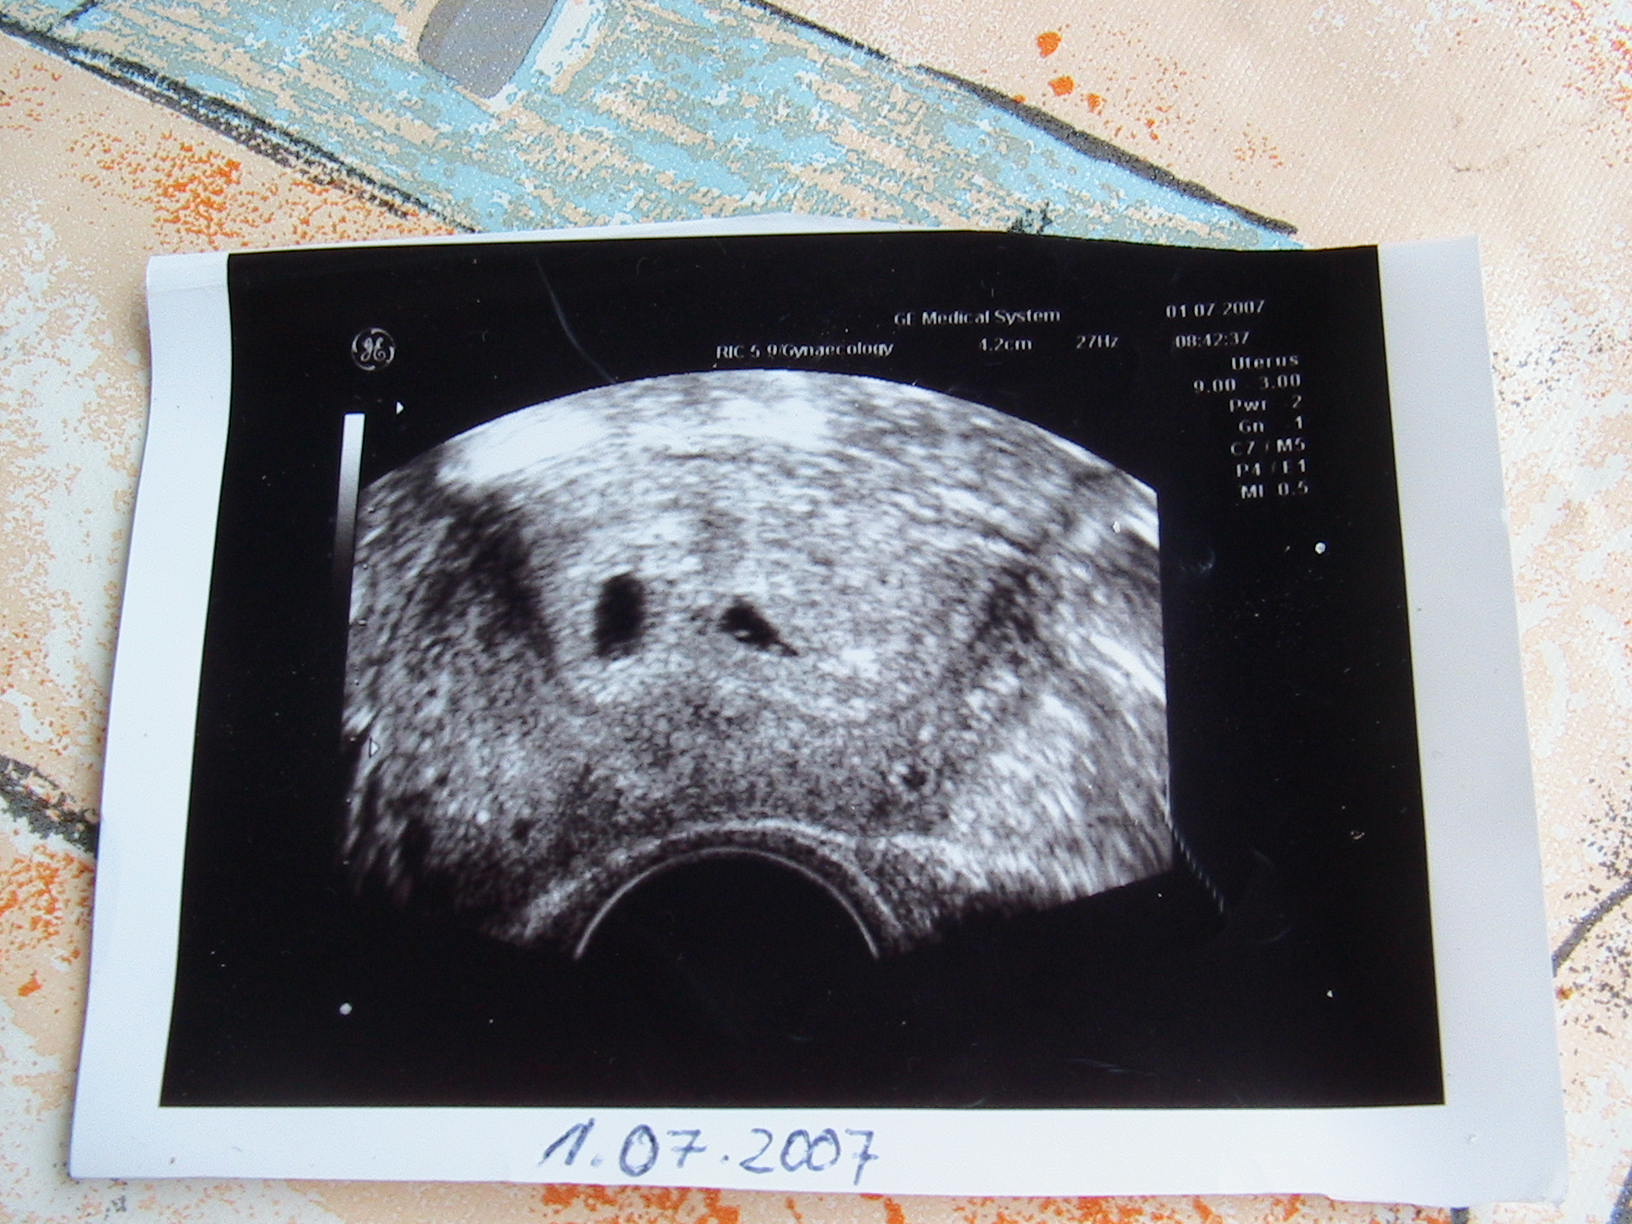

Meine GBS liegt bei 1,0 und ist somit richtig schön kuschelig für ganz viele Krümmel!!

Wir haben ein schönes EI mit 15 mm. Ich soll ab morgen 150 Einheiten spritzen und am Montag nochmal hin! Meine Blutwerte scheinen noch nicht wirklich zu stimmen. Also werde ich mal weiter brüten.